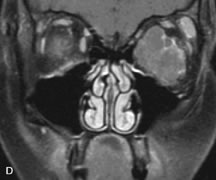

Cavernous hemangiomas appear as well-circumscribed, smooth, usually intraconal masses that are isointense to muscle on T1-weighted images and hyperintense on T2-weighted images (Fig. 12). Patchy early enhancement is typically followed by diffuse, more homogeneous enhancement.39 The internal architecture of the mass, including septation and internal vasculature, may often be appreciated with high-quality orbital imaging.40

Fig. 12. A. T1- and (B) T2-weighted MR scans demonstrate a well-circumscribed intraconal mass causing severe optic nerve displacement. These lesions are usually intermediate in signal intensity on T1-weighted scans and very hyperintense on T2-weighted Images. C and D. Postcontrast fat-suppressed T1-weighted scans demonstrate characteristic patchy intense enhancement that becomes more complete from the initial postcontrast scan (C) to a more delayed scan (D).